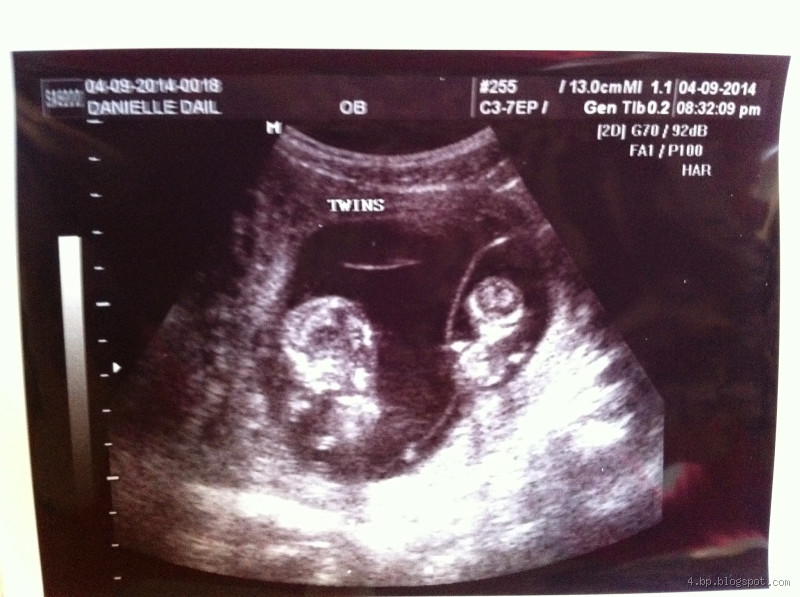

At What Point Can You See Twins on an Ultrasound?

How Early Can You Detect Twins on an Ultrasound?

Okay, so the earliest you can typically detect twins is around the 6th to 8th week of pregnancy. That's when the ultrasound should clearly show two sacs, or if you're really lucky, two embryos with heartbeats! In many cases, a transvaginal ultrasound will be done at this stage, as it’s more sensitive and can offer a clearer picture early on.

The 12-Week Mark: Clearer Images

By the time you're around 12 weeks, the images on the ultrasound become much clearer. This is when the doctor can confirm more definitively whether you’re expecting twins or just one baby. At this stage, the two babies will be more visible, and the doctor might even start giving you details about each one, including their position and individual heartbeats.

So, when can you see twins on an ultrasound? Typically, between 6 and 8 weeks, but the 12-week mark is when things get much clearer. The type of ultrasound and the position of the babies can affect how soon they’re visible. If you think you might be carrying twins, or if there’s a history of twins in your family, it’s exciting to think about the possibility, and ultrasounds will give you a peek into this amazing journey!